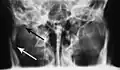

Traditionally, plain films of the mandible would be exposed but had lower sensitivity and specificity owing to overlap of structures. Views included AP (for parasymphsis), lateral oblique (body, ramus, angle, coronoid process) and Towne's (condyle) views. Condylar fractures can be especially difficult to identify, depending on the direction of condylar displacement or dislocation so multiple views of it are usually examined with two views at perpendicular angles.[11]

- Towne's view of a bilateral condyle fracture. White arrow is a fracture on the neck of the condyle. Black arrow shows the condyle pulled to the medial. The same injury can be seen on the opposite side